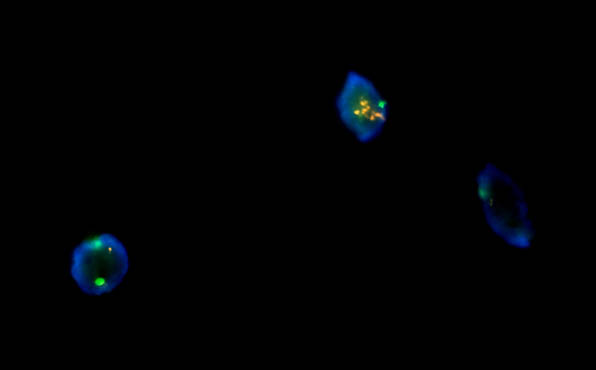

熒光顯微鏡應(yīng)用于試劑FISH檢測

FISH熒光原位雜交產(chǎn)品目前在國內(nèi)主要有三大領(lǐng)域:實(shí)體瘤、血液病和產(chǎn)前/流產(chǎn)診斷。實(shí)體瘤和血液病在醫(yī)院開展FISH檢測較多,與靶向藥物治療相關(guān)的一些探針觀察,如乳腺癌HER-2等。產(chǎn)前/流產(chǎn)診斷,主要是染色體數(shù)目異常或結(jié)構(gòu)異常。如此次北京某公司需要的熒光顯微鏡對試劑FISH樣品進(jìn)行檢測

此次,工程師推薦的全套FISH熒光顯微鏡整套方案包含成像軟件和相機(jī),成像清晰,操作簡便,檢測快速,24小時內(nèi)出結(jié)果,且結(jié)果易觀察,并且重復(fù)性好,空間定位準(zhǔn)確。標(biāo)本來源豐富:間期細(xì)胞、分裂中期細(xì)胞、分化或者未分化細(xì)胞以及死亡或者存活的細(xì)胞都可以被檢測。